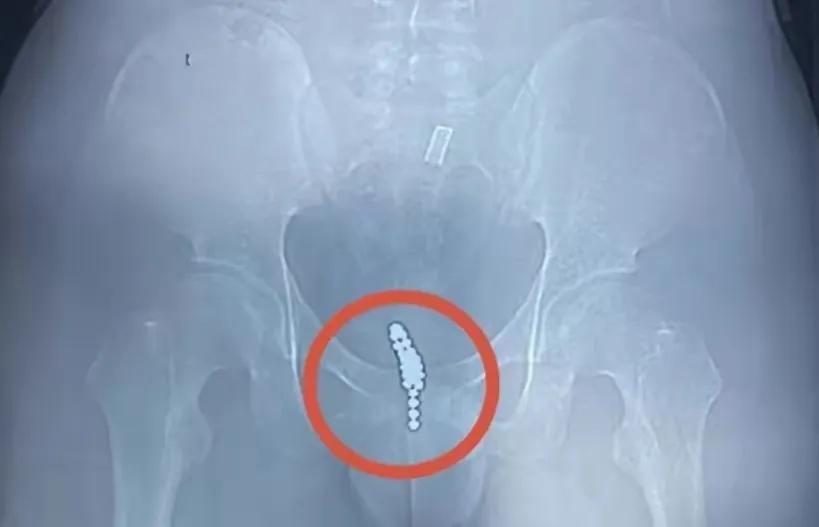

由于好奇,他将一颗“磁力珠”塞入自己的尿道,然而却无法取出,惊慌之下又连塞了几颗,企图利用磁力将珠子给吸出来。

结果连塞了20多颗都没能将磁力珠给吸出来,还出现尿频、尿急和血尿等情况,他无奈只得告诉父母。